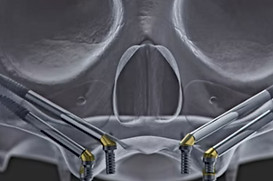

Zygomatic implants are a game-changer for patients with severe bone loss, but mastering this advanced technique requires specialized training. With so many courses available globally, choosing the right one can be challenging.